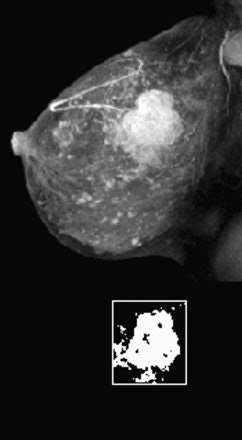

|  |

| Fifty-year-old woman with invasive ductal carcinoma, grade III, studied while undergoing neoadjuvant chemotherapy treatment. MRIL was performed using contrast-enhanced 3D fast gradient-recalled echo-pulse sequence. Patients presented with 22 cm3 (4.7-cm diameter) tumor. Significant reduction in MRI volume was evident after one cycle of chemotherapy (30% decrease) and by end of treatment (88% decrease). Patient had 2.2 cm of residual disease and one involved lymph node at surgery, and continues to be disease-free 20 months after surgery.  |